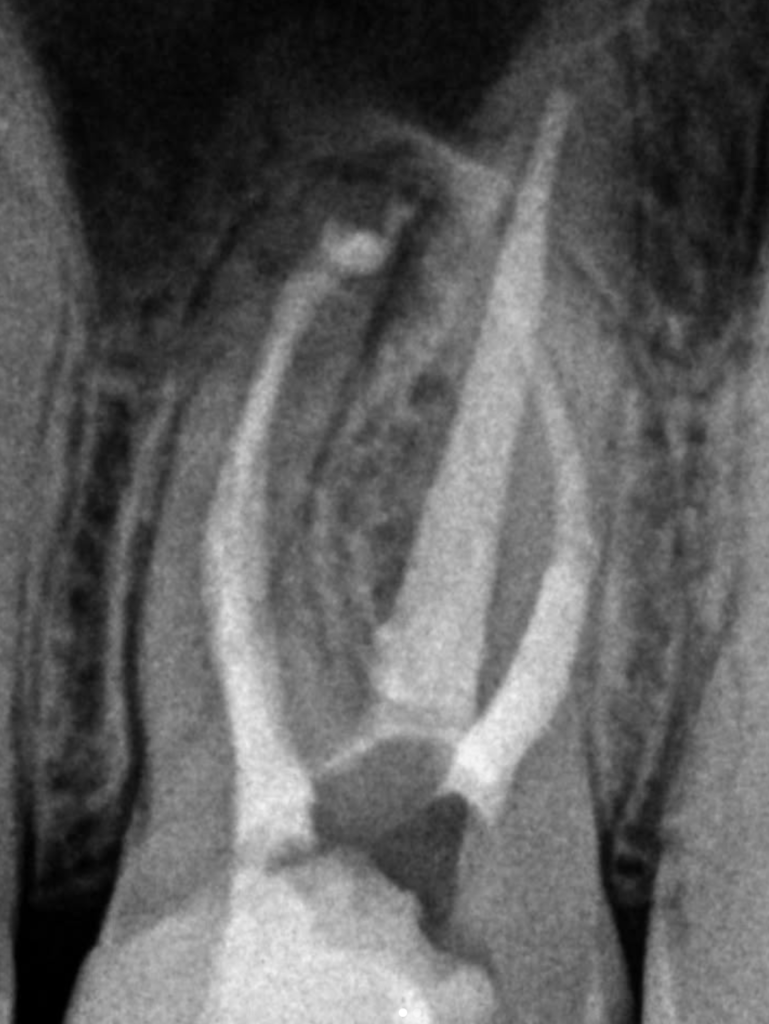

❗️Jeśli ząb był już leczony endodontycznie, ale występują dolegliwości, nie zawsze musi oznaczać to usunięcia zęba❗️

Często udaje się uratować zęba🦷✅